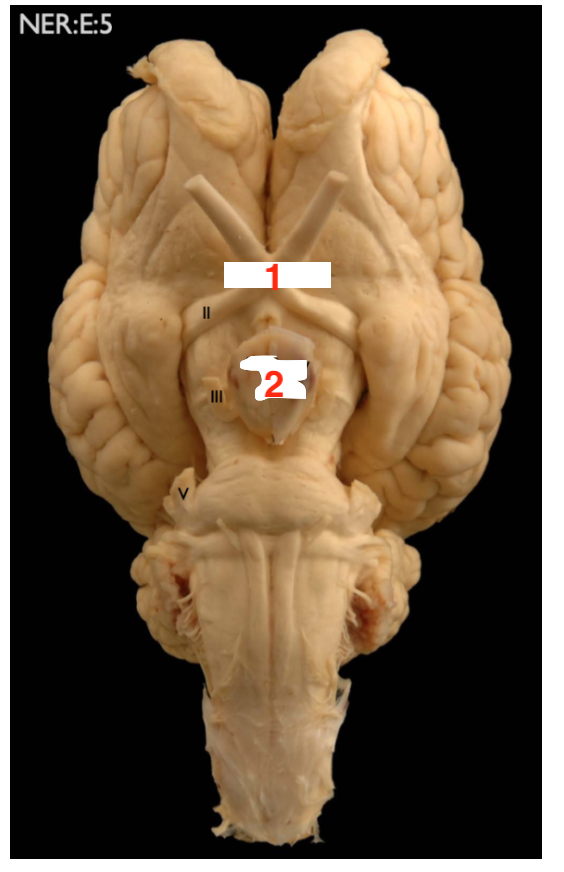

Name the following structures that are shown in the image: (for 1. name the system that the two structures in the green circle make up)